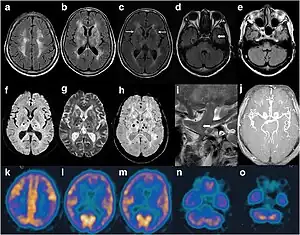

| Cranial imaging of an FFI patient. In the MRI, there are abnormal signals in the bilateral frontoparietal subcortical area. MRA showed smaller distal branches of cerebral arteries. | |